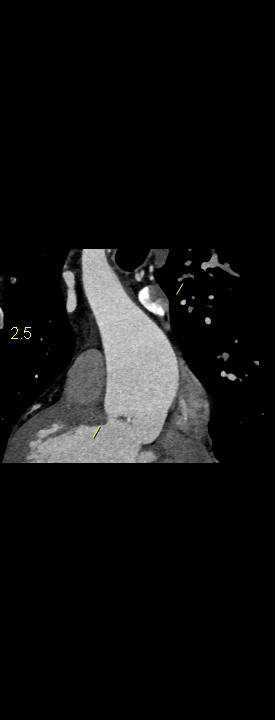

Figurile 1-5: reconstrucții multiplanare din achiziție angioCT aorta toracică

Discuţie caz nr 109: Pacient cu suspiciune de coarctaţie de aortă – are indicație de angioCT aortă toracică; medicul radiolog la acești pacienți este indicat să efectueze investigația cu sincronizare ECG deoarece coarctaţia de aortă poate fi asociată și cu bicuspidie de valvă aortică, mai ales că la acest pacient ecografia cardiacă descria creștere de calibru a aortei ascendențe. Pe reconstrucția cine în planul valvei aortice din achiziția cardioCT cu sincronizare ECG se remarcă o valvă aortică morfologic tricuspidă, funcțional bicuspidă ce asociază ectazie de aortă ascendentă și coarctaţie de aortă descendentă cvasicompletă cu dezvoltare de circulație colaterală intercostală și mamară internă.